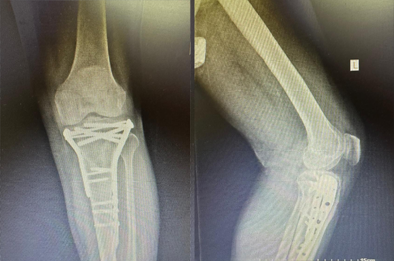

Tibial condyle fracture